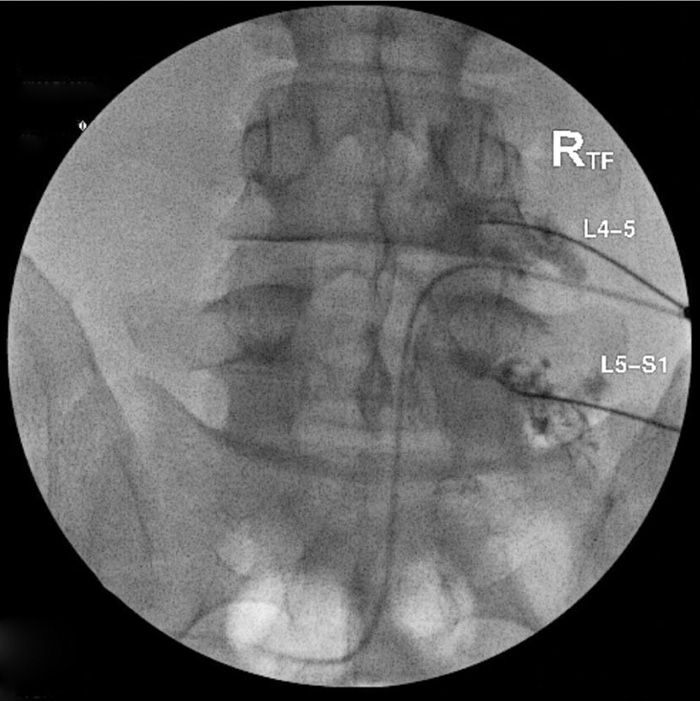

Dorsal Root Ganglion Block / Transforaminal Epidural.

Dorsal Root Ganglion Block. The diagnostic nerve root blocks were performed twice, with pain reduction of 50% defined as a positive block. Selective dorsal root ganglion blocks (drgbs) have been used in these situations to aid the diagnostic process, although their use remains controversial.

This ganglion contains nerves that carry sensation. Dorsal root ganglion blocks (nerve root injections) are a procedure in which the spinal nerve roots are injected with local anaesthetic and steroid to treat pain caused by irritation and. The sensory nerves enter through a hole referred to as the intervertebral foramen.